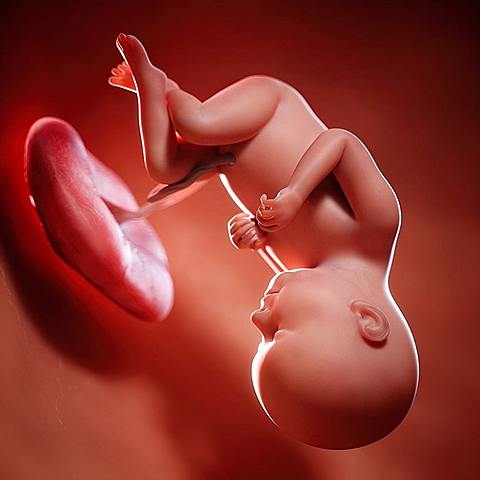

• Period: 26 to 40

3er Trimestre

-Aumento entre 3kg y 5 kg.

-Frecuentes ganas de orinar.

-Aumento de transpiración.

-Contracciones uterinas de Broxton-Hicks.

-Cansancio y dolores de espalda.

Desarrolla todo lo relacionado con los ojos, huellas de los pies y pulmones funcionando completamente

• Semana 30

30

Semana 30

-El feto a estas semanas empieza a ubicarse en la posición definitiva que tendrá al nacer, que en la mayoría de los casos es con la cabeza hacia abajo a pesar de que puede cambiarla hasta el momento del parto.